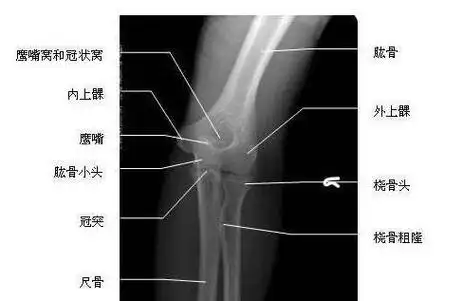

盼文的胳膊,博客文章,手臂骨折后的快速康复训练方法